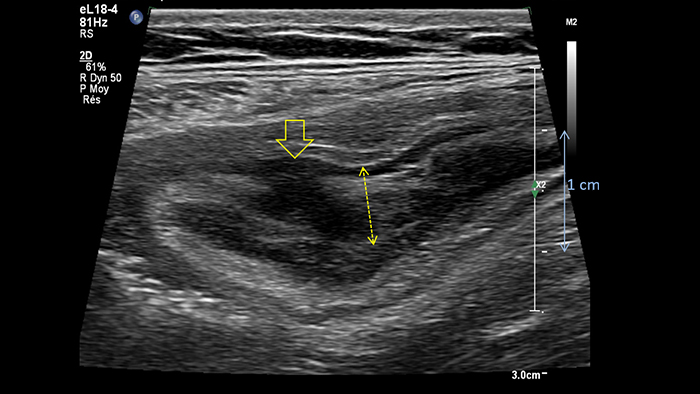

Ces images précises des lésions des couches pariétales forment la base de l’interprétation des changements induits par l’inflammation des parois intestinales et par conséquent de la différenciation entre la maladie de Crohn et la rectocolite hémorragique. L’exploration avec la technologie MFI (MicroFlow Imaging) constitue la deuxième étape. Il s’agit de reconnaître l’aspect de l’hypervascularisation induite par des épisodes inflammatoires actifs. La paroi intestinale normale semble comporter peu de microvaisseaux détectables, uniquement à l’interface de la muqueuse et de la sous-muqueuse, et dans le tissu adipeux mésentérique adjacent. Inversement, la paroi inflammatoire présente de nombreux microvaisseaux. La distinction entre les images d’artefacts de mouvement et les microvaisseaux circulants est alors un point essentiel nécessitant un ajustement parfait des paramètres de détection des micro-flux (voir les boucles, diapositive 8). La comparaison des 4 images suivantes de la maladie de Crohn met en évidence des différences claires qui devraient être interprétées comme étant représentatives des différents états inflammatoires. L’image 1 ne comporte aucun vaisseau visible, ce qui correspond probablement à une absence d’activité. L’image 2 présente quelques vaisseaux ; nous pouvons en conclure que cela correspond à une activité modérée. L’image 3 comporte un plus grand nombre de vaisseaux, signe probable d’une activité intense. L’image 4 présente encore plus de vaisseaux de type pulsatile, ce qui évoque probablement une activité très intense.

No vessel no activity ?